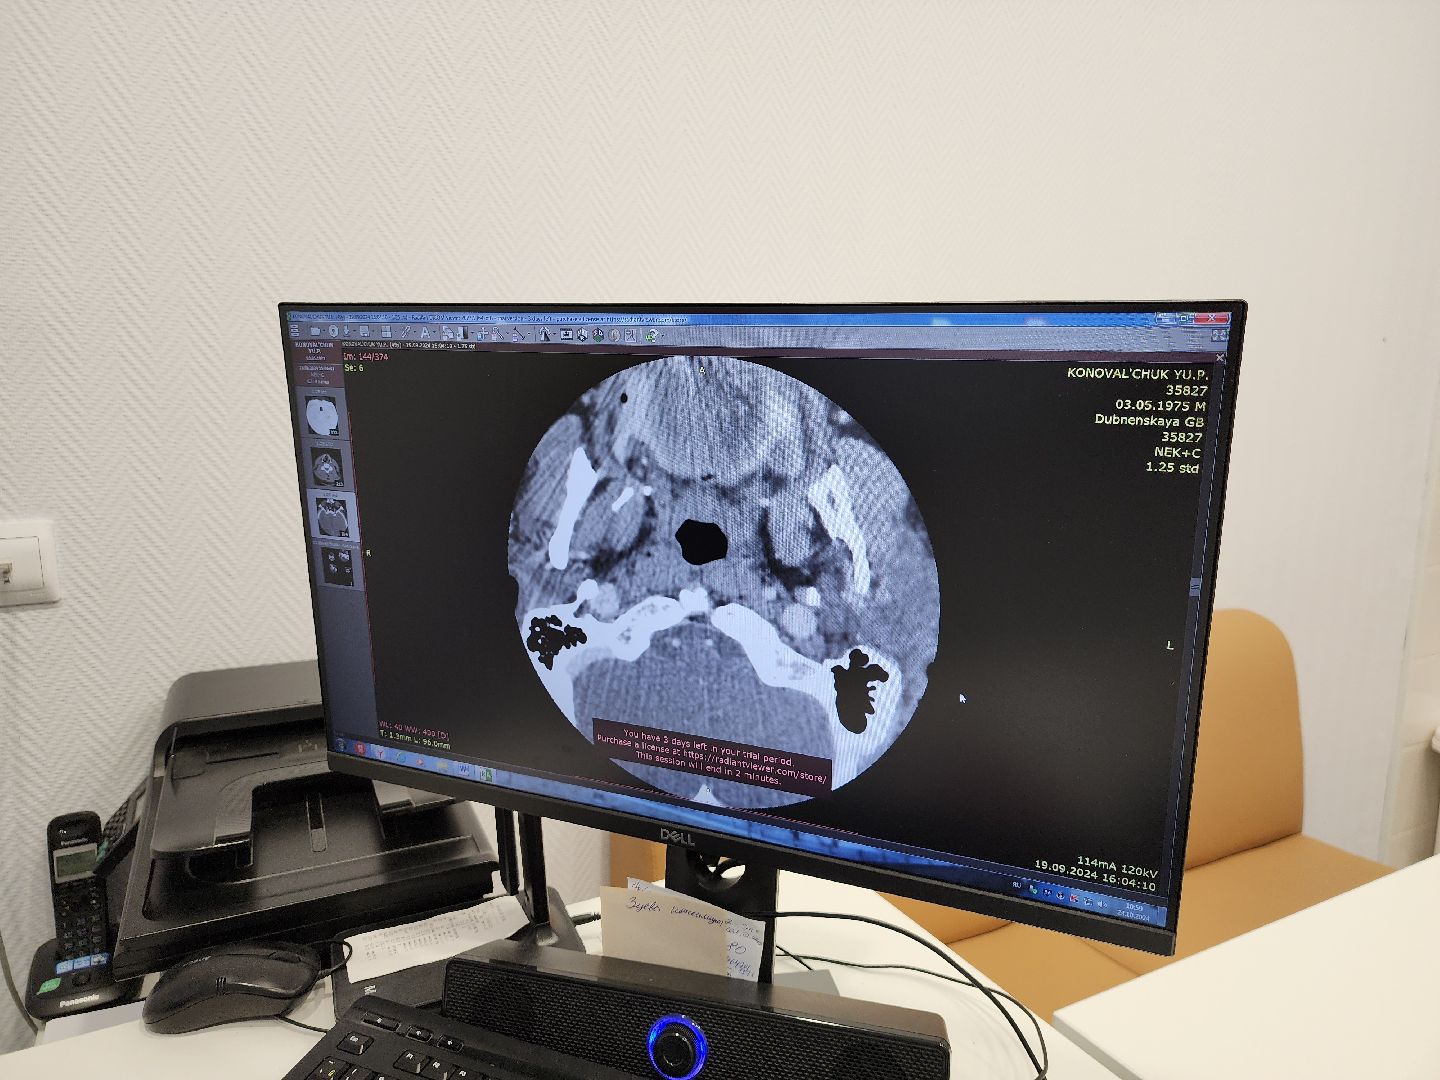

Изначально пациент обратился с жалобами на сердце. Бляшку в сонной артерии обнаружили с помощью компьютерной томографии. С пациентом работали группа врачей-хирургов, анестезиологов, кардиологов и неврологов. Операция прошла в штатном режиме. Пациент уже выписан на амбулаторное наблюдение и чувствует себя хорошо.